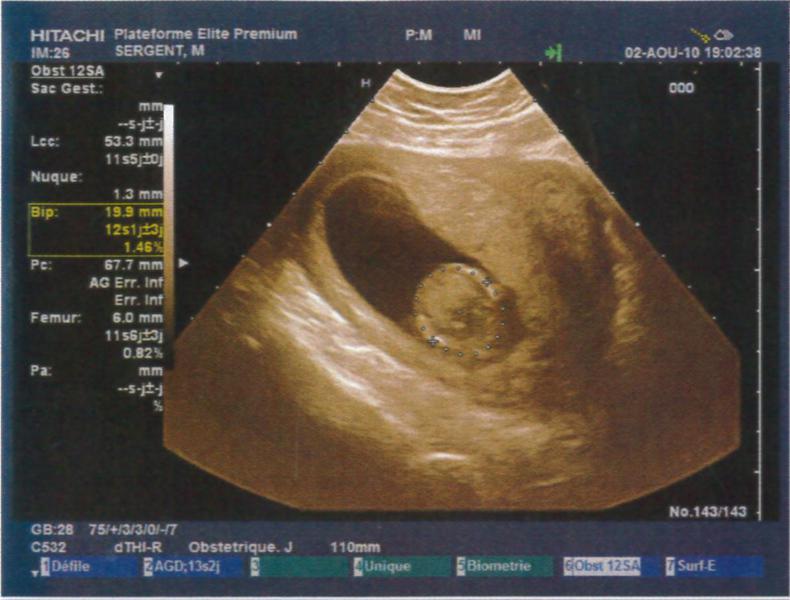

Je suis à 12SA soit 10SG, j'ai fait mon écho hier soir et tout va super bien !!! Je suis trop heureuse je vais vraiment pouvoir vivre ma grossesse à fond !! La nuque est parfaite, à vérifier par le test de la trisomie la semaine pro en même temps que la déclaration !!

Je vous met les photos des échos mais je trouve que l'on ne voit rien par rapport aux superbes images que nous avons vues !! Mais c'est pas grave, on a un super souvenir quand même !!

• echo3.jpg

echo3.jpg

52.7 KB · Affichages: 69